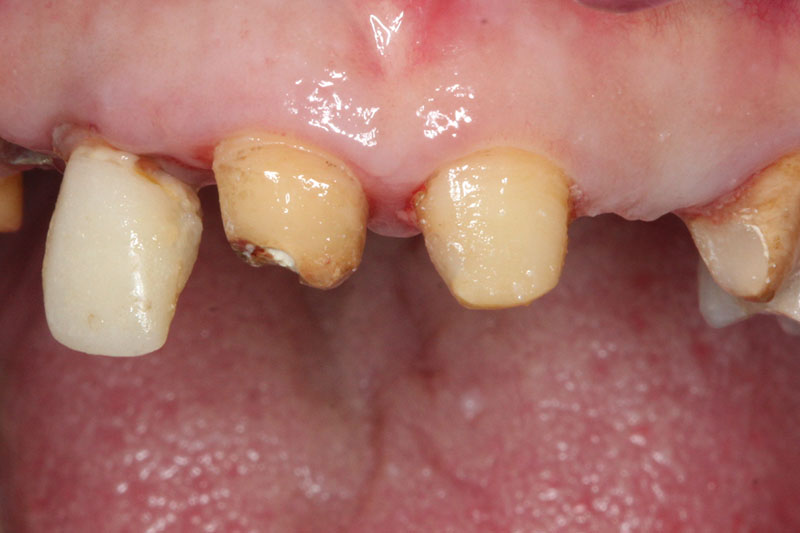

缺牙多顆

案例一

術前